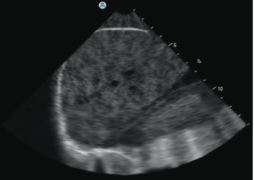

- A reliable ultrasound display of anatomy per probe position, incorporating common ultrasound imaging attributes and artefacts.

BEDSIDE ECHOGRAPHY MODULE:

The Bedside Echocardiography Module incorporates 10 hands-on tasks and clinical cases, accompanied by comprehensive didactics.

The simulation environment combines high level of realism with advanced educational aids, featuring:

- Step by step dedicated Bedside Echocardiography tasks promoting self learning of the complete protocol as well as anatomy structures recognition.

- Featuring basic standard views complemented by more challenging views such as suprasternal, IVC, apical 2 chambers, apical 3 chambers and more.

- Diverse virtual patient cases taking after real patients, ranging from normal, through slightly abnormal to distinct pathologies.

- Incorporated ECG, Cine loops recordings, calliper measurements and more.

- The clinical cases present scenarios and complaints such as chest pain, mild to severe dyspnea, diverse arrhythmia, diaphoresis, weakness and more.

- With findings such as: normal heart, mitral regurgitation, aortic dissection, pericardial effusion, pulmonary embolism (PE), dilated cardiomyopathy (DCM), Myocardial infarction (MI), tamponade and more.